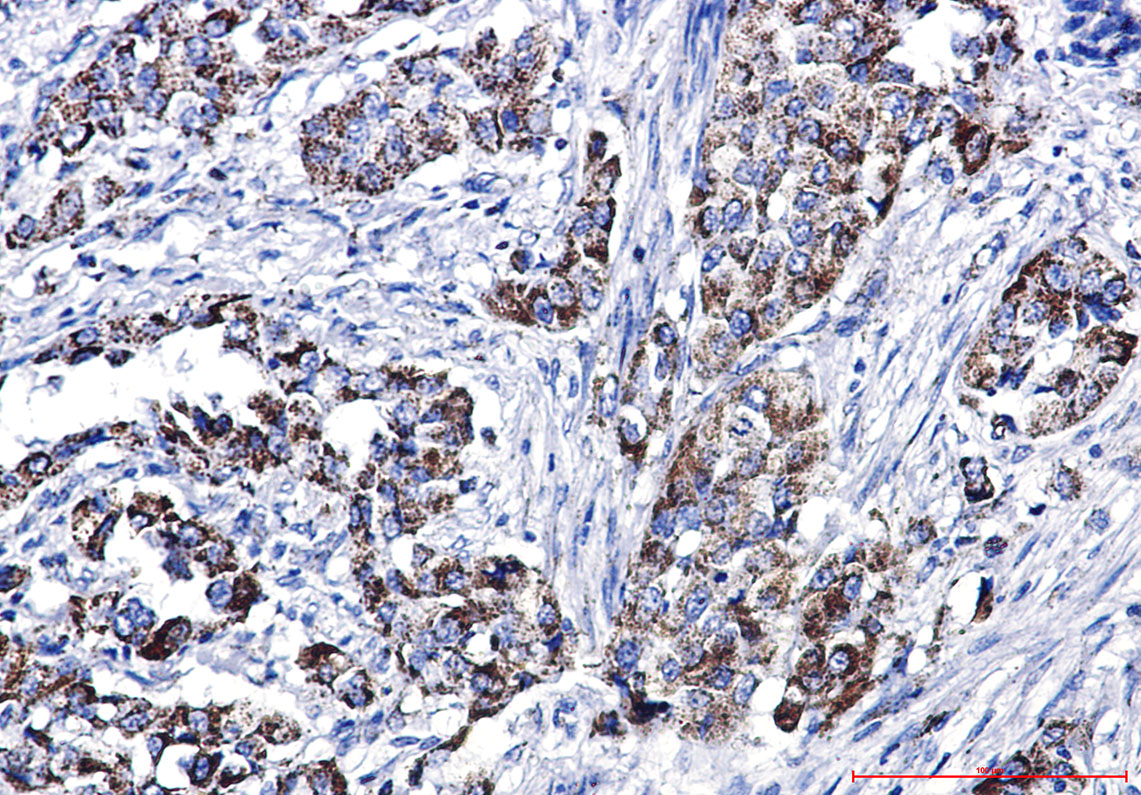

IHC 1/50-1/100 Human,Mouse,Rat

**摘要**: 本研究利用特异性抗GLS1抗体(克隆D8T2D)通过Western blot和免疫组化分析三阴性乳腺癌细胞中谷氨酰胺酶的表达。发现GLS1高表达与细胞增殖相关,抑制其活性可阻断肿瘤生长,提示GLS1抗体在癌症代谢研究中的诊断价值。

**摘要**: 使用兔源多克隆抗GLS2抗体(Abcam ab156876)对肝癌组织进行免疫组化分析,发现GLS2低表达与患者预后不良相关。研究表明GLS2可能作为肝癌的生物标志物,其抗体在病理诊断中具有潜在应用。

These antibodies are widely used in techniques like Western blotting, immunohistochemistry, and immunofluorescence to localize glutaminase in tissues or cells. Their applications extend to cancer research, where glutaminase upregulation is linked to tumor growth and metastasis, as well as neurological studies, given glutamate's role as a neurotransmitter. Specific antibodies against GLS (e.g., targeting GAC) have become pivotal in developing therapeutic strategies, including small-molecule inhibitors.